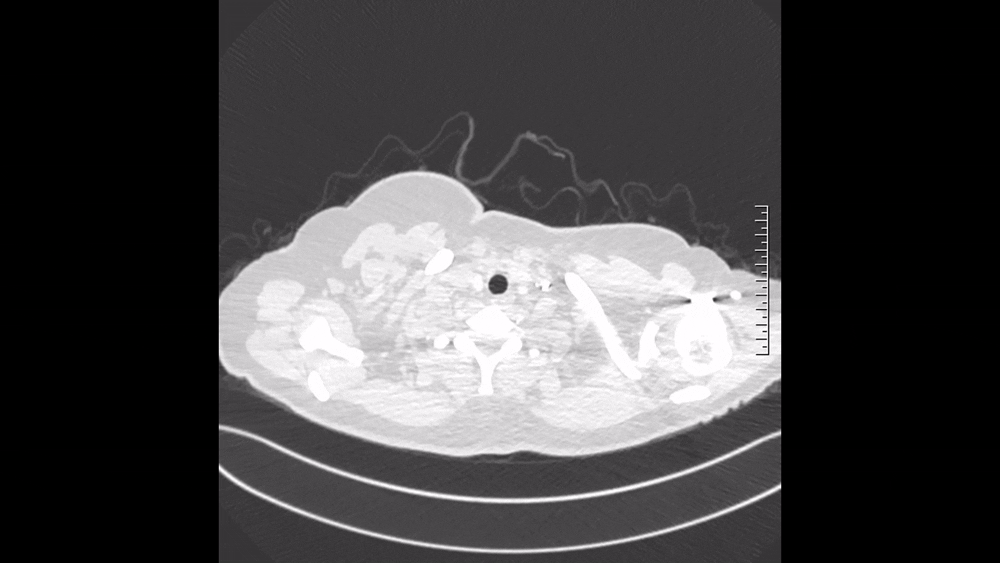

图3 2024.11.4 CTPA肺窗

仔细阅读CTPA:肺窗可见多发磨玻璃影,马赛克征象,这是肺血流灌注不均的表现(图3);纵隔窗可见肺动脉主干增粗,提示肺动脉压力升高;右肺上叶、中叶血管纹理稀疏,多个肺动脉亚段及分支(RA1、RA2、RA3、RA4、RA5、RA10、LA4、LA5为著)狭窄、闭塞病变,这些提示肺动脉慢性血栓表现(图4)。